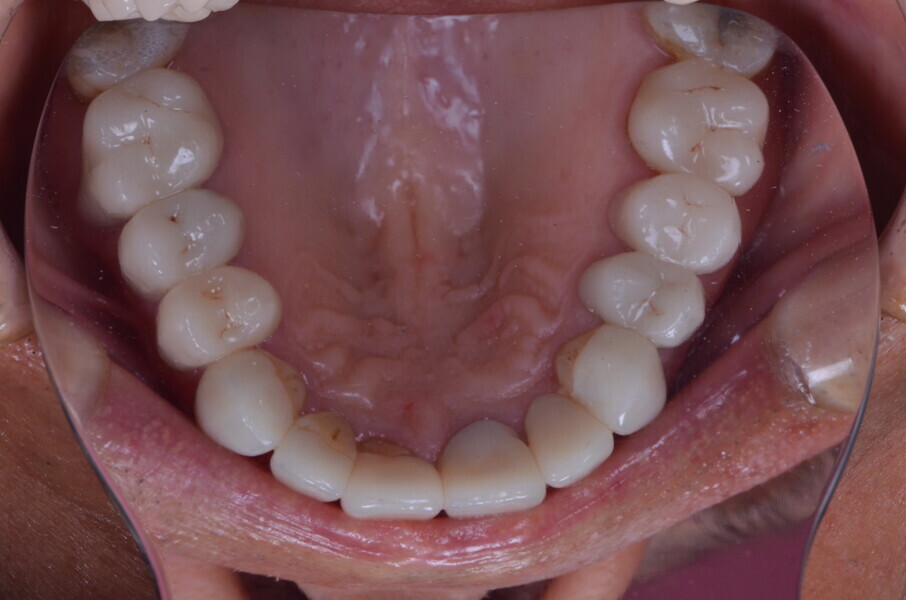

Figure 30 Madibular occlusal view